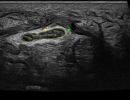

- Brachial Plexus in the neck area

- Peripheral Nerves of the Upper Limbs (radial, ulnar, and median nerves)

- Peripheral Nerves of the Lower Limbs (femoral, sciatic, tibial, peroneal nerves)